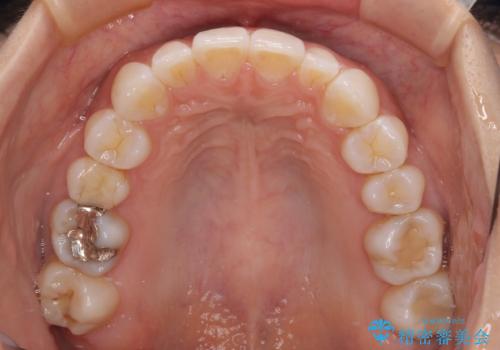

【モニター】前歯のデコボコと小さい前歯 インビザライン矯正とオールセラミッククラウン補綴治療

- 前歯の歯並びと生えてきたときから小さい前歯を気にして来院された患者様です。

上下前歯の歯列不正はインビザラインにより整え、その後に、矮小歯の前歯をオーダーメイドタイプのオールセラミッククラウンにて補綴治療することとしました。

インビザライン矯正の場合、矮小歯を矯正治療後にセラミックとするかどうかを矯正治療開始前に決める必要があるため、悩んでしまう方が多いです。

セラミッククラウンにて大きさを変更することを前提に矯正治療を開始したため、大変満足のいく仕上がりとなりました。